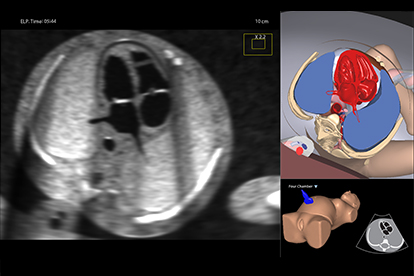

Simbionix Ultrasound Mentor is the answer to the growing need for ultrasound training among multiple medical specialties. This modular simulation platform enables easy manikin rotation (male, female, pediatric and interventional), and offers diverse applications for a range of specialties such as OB/GYN, Point-of-care Ultrasound (POCUS) and Echocardiography.

Ultrasound Mentor accelerates the development of basic to advanced technical and cognitive skills, by providing not only the probe manipulation training, but also a didactic environment enabling structured, self-guided learning including step-by-step instructions and educational aids such as 3D anatomical map and probe positioning assistant, all backed up with our progress monitoring tool MentorLearn.

- Advanced diagnostic tools, including Color Doppler, CW, PW, M-mode, and measurements

Advanced Echo Module

TEE Module